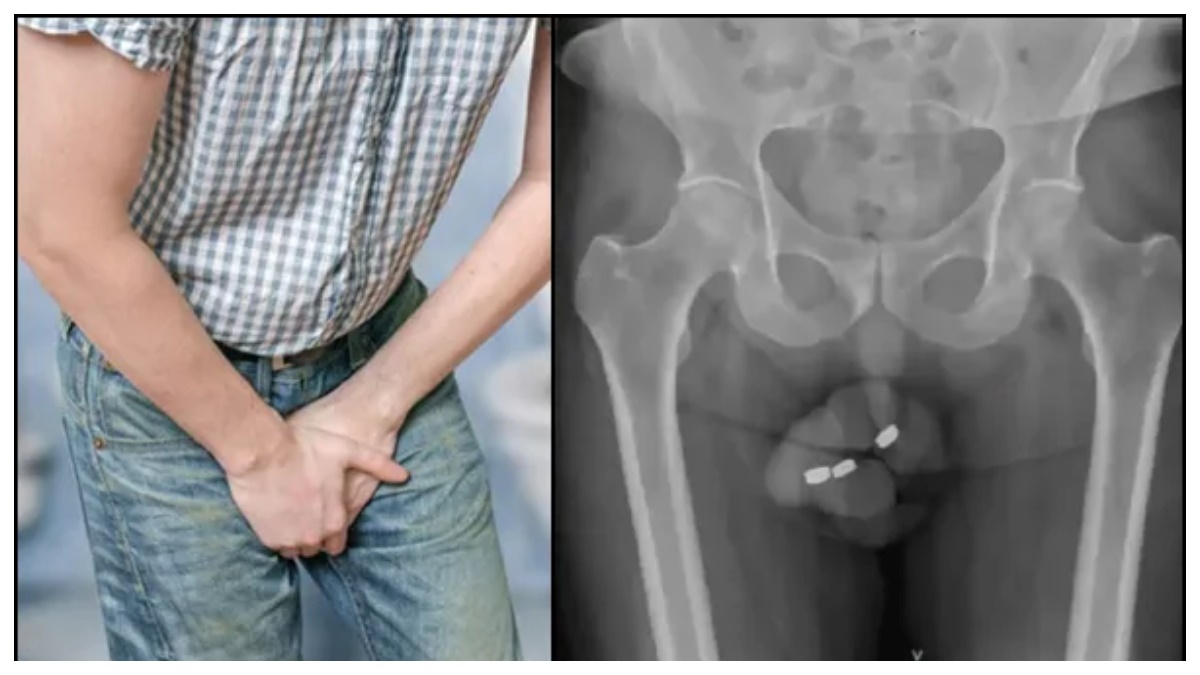

ఆస్ట్రేలియాలో 73 ఏళ్ల వృద్ధుడు పెద్ద షాక్ ఇచ్చాడు. ఆ వృద్ధుడి పురుషాంగంలో 3 బటన్ల పరిమాణంలో బ్యాటరీ ఇరుక్కుపోయింది. వైద్యులు ఈ బ్యాటరీని తొలగించారా? పురుషాంగంలోకి బ్యాటరీ ఎలా వచ్చింది? ఇప్పుడు ఆ వృద్ధుడి పరిస్థితి ఏంటో వివరంగా చూద్దాం.

ఆస్ట్రేలియాలోని 73 ఏళ్ల వ్యక్తి పురుషాంగంలో 3 బటన్ల బ్యాటరీ ఇరుక్కుపోవడంతో ఆసుపత్రికి తరలించారు. ఈ బ్యాటరీ ఎలా వచ్చిందో తెలుసా? ఈ వృద్ధుడే పురుషాంగంలోకి బ్యాటరీని ఎక్కించాడు. లైంగిక ఆనందం కోసమే ఇలాంటి పని చేశాడని అంటున్నారు. అతను ఇప్పటికే చాలాసార్లు ఇలా చేశాడు. అయితే ఈసారి బ్యాటరీ కాస్త పెద్ద పనే ఇచ్చింది. ఆయన కూడా డాక్టర్లతో ఏకీభవించారు.

ఆసుపత్రిలో వైద్యులు అతడిని పరీక్షించగా, యూరిటెరల్ నెక్రోసిస్ ప్రాంతంలో బ్యాటరీని ఉంచారు. ప్రపంచంలో ఇలాంటి కేసు ఎప్పుడూ నమోదు కాలేదు. ఇదే మొదటిసారి. మరియు ఈ వృద్ధుడు తన పురుషాంగంలో బ్యాటరీ ఇరుక్కున్న 24 గంటల తర్వాత ఆసుపత్రికి వచ్చాడు. పురుషాంగంలో విపరీతమైన నొప్పి, మూత్ర విసర్జనలో ఇబ్బంది వంటి అనేక సమస్యలు కూడా ఉన్నాయి.

కానీ బ్యాటరీలోని యాసిడ్ లీక్ అయి అతనికి నెక్రోసిస్ ఏర్పడింది. నెక్రోసిస్ అనేది కణజాలం చనిపోయేలా చేసే ఒక పరిస్థితి. నిపుణుల అభిప్రాయం ప్రకారం, నెక్రోసిస్ మరమ్మత్తు చేయబడదు మరియు అది ప్రాణాంతకం కావచ్చు.

బ్యాటరీని మరియు చుట్టుపక్కల చనిపోయిన కణజాలాన్ని తొలగించడానికి వైద్యులు శస్త్రచికిత్సను పరిశీలిస్తున్నారు. కానీ బ్యాటరీని అంత తేలిగ్గా తీసేయలేరు.కానీ వారు ఎలోగోలా కాస్త కష్టపడ్డారు. బ్యాటరీని తొలగించే శస్త్రచికిత్స సమయంలో, బ్యాటరీ నుండి నల్లటి ద్రవం లీక్ అయి పురుషాంగంపై తీవ్ర ప్రభావం చూపడంతో వైద్యులు వృద్ధుడి నుండి పురుషాంగంలో ఎక్కువ భాగాన్ని తొలగించాల్సి వచ్చింది.

ఈ ద్రవం లీక్ కావడం వల్ల ప్రభావితమైన ప్రాంతం పూర్తిగా చికిత్స పొందేందుకు 6 నెలల వరకు పడుతుంది. అదే సమయంలో, ఈ వృద్ధుడి పురుషాంగం బాగా ప్రభావితమైందని, దాన్ని చికిత్స చేయలేమని వైద్యులు తెలిపారు. ఇప్పుడు ఆ వృద్ధుడు ఎలాంటి సుఖాన్ని పొందలేకపోతున్నాడు.